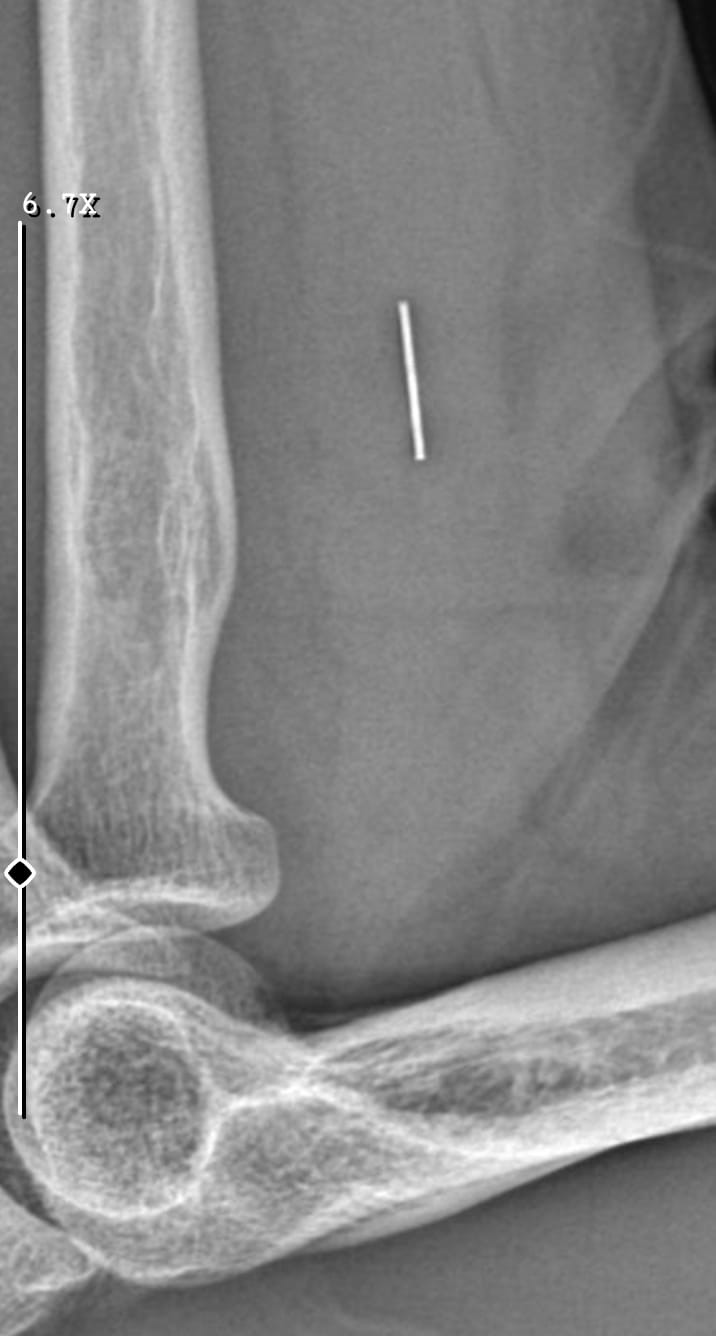

Edinilen bilgiye göre, 7 Haziran 2025'te Kurban Bayramı dolayısıyla bıçak temizlerken sağ el başparmağını kesen Nurettin Güleryüz (34), bir özel hastanenin acil servisine başvurdu. İddiaya göre, hastanede detaylı tetkik yapılmadan pansuman uygulanan Güleryüz'e ilaç reçete edilerek taburcu edildi. Şikayetlerinin devam etmesi ve kanamanın durmaması üzerine ertesi gün aynı hastaneye tekrar giden Güleryüz'e bu kez dikiş atıldı. Parmağını hareket ettirememesi üzerine 19 Haziran'da Gebze'deki başka bir özel hastaneye başvuran Güleryüz, tendon yaralanması şüphesiyle tedaviye alındı. Farklı tarihlerde yapılan EMG ve MR tetkiklerinde sinir hasarı ile tendon kopması tespit edilen hasta, 2 Eylül'de ameliyat edildi. Süreç içerisinde parmağın çürüdüğü ve kurtarılamayacağının belirtilmesi üzerine Güleryüz, başvurduğu başka bir hastanede ampute operasyonu geçirdi. Öte yandan, ameliyatların ardından ağrıları devam eden Güleryüz'ün kolunda metal parça bulunduğu ve bu parçanın parmak bölgesinden dirseğe doğru ilerlediği öne sürüldü. Ayrıca, fabrikada temizlik personeli olarak çalışan Nurettin Güleryüz'ün hastane sürecinde işten çıkarıldığı da öğrenildi.

İkinci hastanedeki ameliyatların ardından kolunda ağrılar hissettiğini söyleyen Güleryüz, sözlerini şöyle noktaladı: "Doktorlara bileğime doğru ağrılarım olduğunu sürekli ifade etmeme rağmen beni dinlemediler. Sonradan kolumda metal kaldığını öğrendik. Bunun ihmal olduğunu düşünüyoruz. Çünkü kola metal nasıl girebilir? Ben 9 aydır çalışamıyorum. Kalp rahatsızlığım sebebiyle yüzde 46 engelliyken şu anda yüzde 75 engelli durumuna düştüm. Erken emeklilik dilekçesi verdim ancak henüz sonuç gelmedi. Bu konuda çok mağdurum. Yetkililerin bunu duymasını istiyorum. Savcılığa suç duyurusunda bulunduk. Yaklaşık 9 aydır henüz soruşturma izni gelmedi. Süreci bekliyoruz, henüz dava açılmış değil. Kolumda bırakılan metal ilerliyor. Pazartesi günü bunun için de operasyon geçireceğim. Çıkarılıp çıkarılamayacağı net değil. Elimde titremelerim var, çalışamıyorum ve işveren tarafından işten çıkarıldım. Yetkililerden destek ve konunun incelenmesini talep ediyorum."